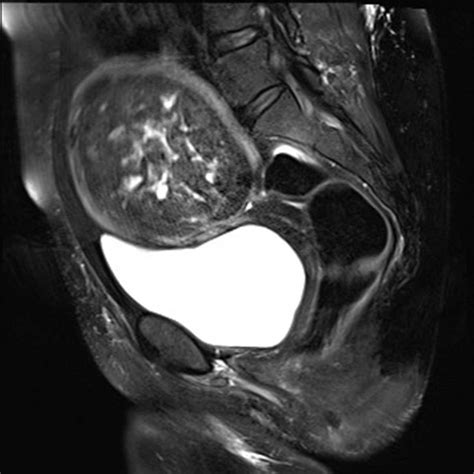

Ultrasound is usually the first-line imaging modality. It can clearly visualize the size, location, and internal texture of the fibroid. In cases of degeneration, the ultrasound might show altered echogenicity—meaning the fibroid does not look uniform. If further clarity is required, an MRI (Magnetic Resonance Imaging) is the gold standard. MRI provides highly detailed images that can differentiate between various types of degeneration, such as red degeneration versus cystic changes, by assessing how the tissue responds to signal intensities.